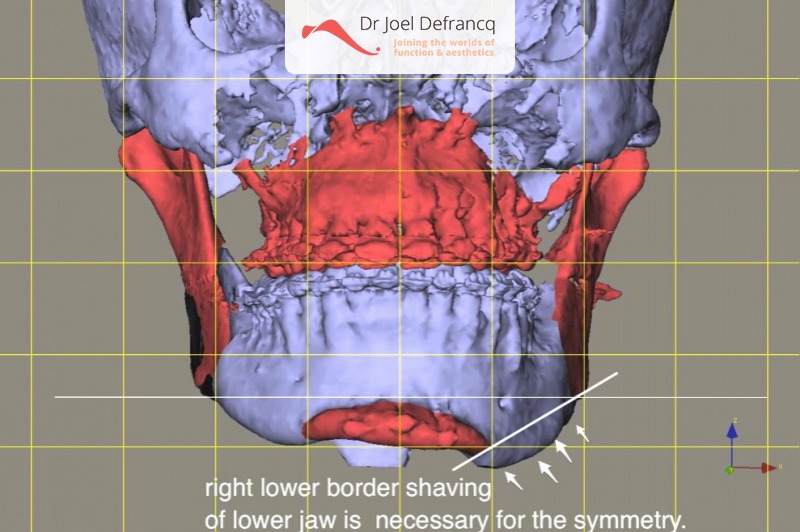

Diagnose van het gezicht

- Te korte bovenkaak

Kaakchirurgie

- Verlenging onderkaak (BSSO)

- Verlenging bovenkaak (Le Fort I)

- Vertikale verlenging bovenkaak (Le Fort I)

- Kinchirurgie

- Redo